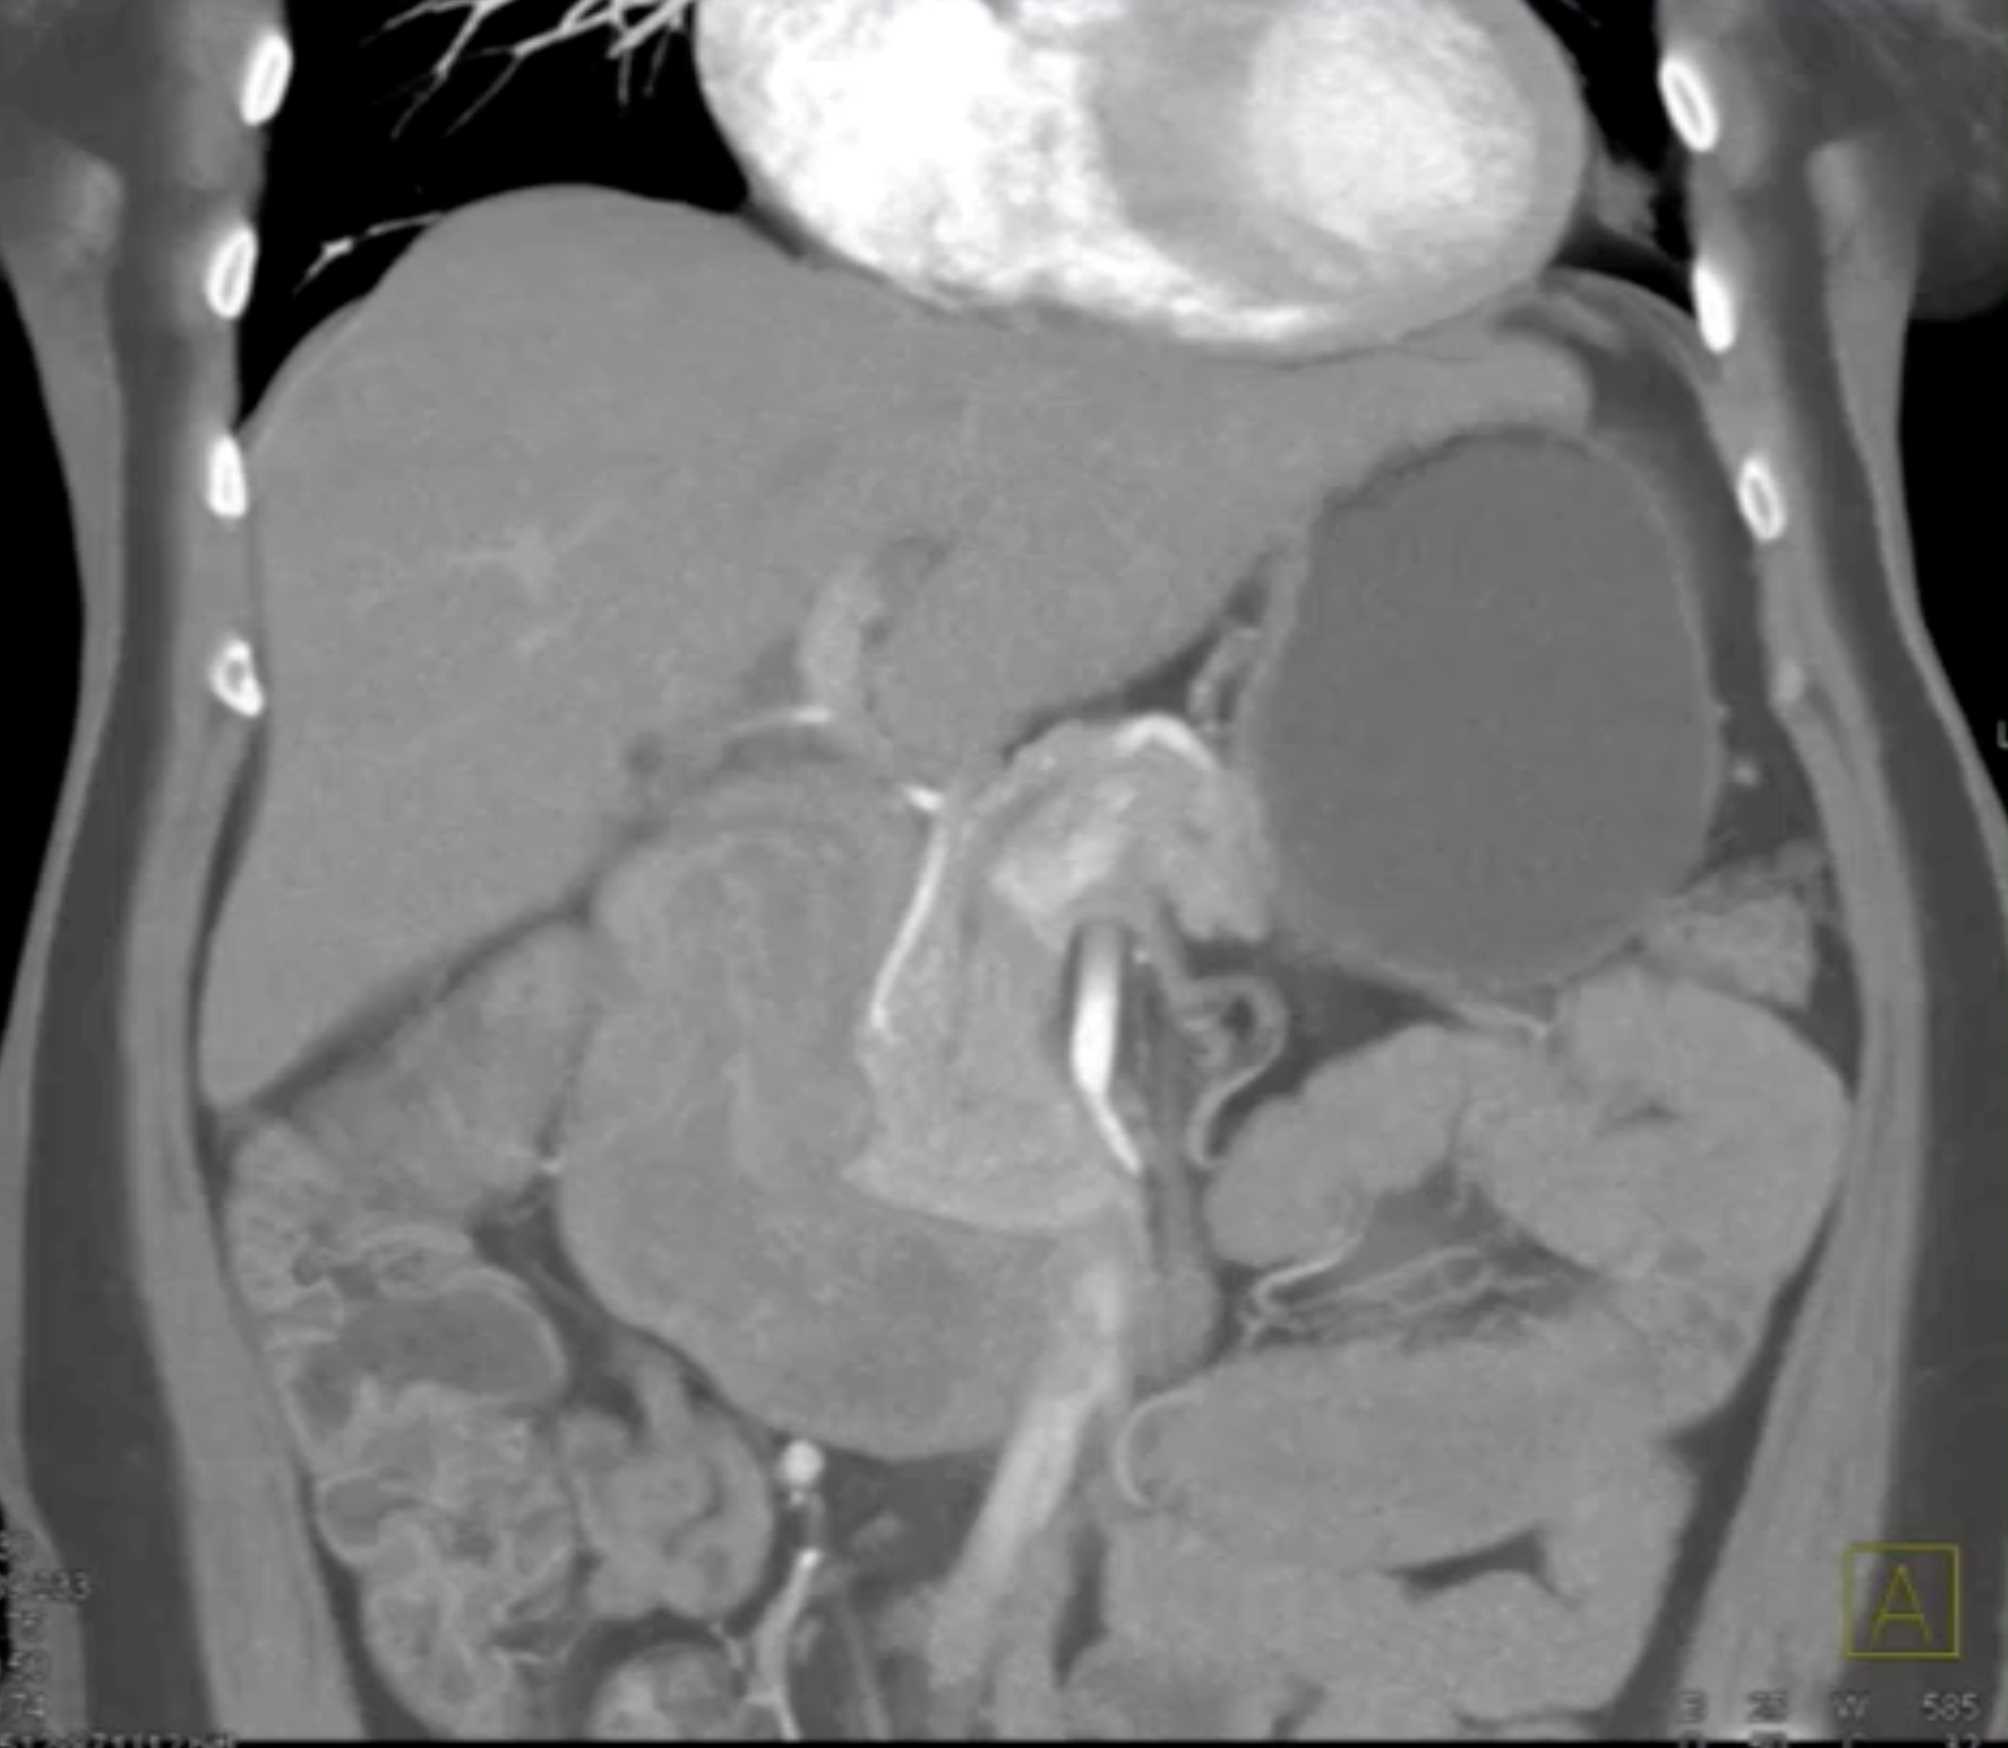

Lagre Gastric GIST Tumor